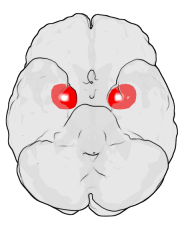

코로나 팬데믹, 사회적 고립, 그리고 현대인의 불안한 삶 속에서 다시 주목받는 뇌 구조가 있습니다. 바로 편도체입니다. 편도체는 작은 아몬드 모양을 하고 있으며, 공포·불안·사회적 유대 등 인간의 감정을 다루는 핵심 기관으로 진화의 긴 역사를 품고 있습니다. 본 글에서는 편도체의 구조와 기능, 진화적 의미, 공포와의 관계, 정신질환에서의 이상, 그리고 최신 뇌과학 연구를 바탕으로 그 역할을 심도 있게 살펴보겠습니다.

편도체는 변연계에 속하며, 해마와 가까운 측두엽 내측에 위치한 작은 집합체입니다. 아몬드(amygdala)라는 이름은 그 형태에서 유래했는데, 크기는 작지만 기능은 막대합니다. 편도체는 외부 감각 자극을 빠르게 평가하고, 위험이나 위협을 감지할 때 즉각적인 생리 반응을 일으킵니다. LeDoux(1996)의 연구에 따르면 편도체는 ‘저속 경로’(시상→편도체)를 통해 시각 정보가 전전두엽에 도달하기 전에도 빠르게 반응합니다. 이는 뱀이나 총과 같은 위협적인 자극을 본능적으로 회피하도록 돕습니다. 또한 편도체는 단순한 공포 감지뿐 아니라, 사회적 표정 해석, 기억의 정서적 강화에도 관여하는 것으로 밝혀졌습니다.